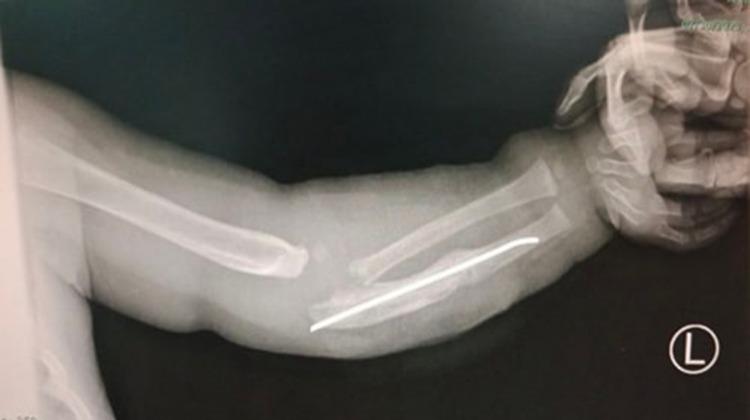

We present a case of a 1-year-old girl, diagnosed with CIPA, admitted to our center complaining of wound discharge and fever from a previously repaired left forearm fracture with nail insertion, which was found to be infected after a failed trial of nail removal. A multidisciplinary- management from anesthesia, orthopedics, ophthalmology, and pediatrics was conducted. The patient underwent successful nail removal, wound debridement, and radius bone reduction with the appropriate anesthetic protocol that did not include analgesic medications. The follow-up course was uneventful with proper alignment and virtually stable health status, with no apparent skeletal or ocular complications.

我们报告一例1岁女童,诊断为CIPA,因之前插入髓内钉的左前臂骨折修复术后伤口渗液和发热入住我院。在尝试取出髓内钉失败后,发现伤口感染。我们实施了麻醉科、骨科、眼科和儿科的多学科管理。在未使用镇痛药物的适当麻醉方案下,患者成功取出髓内钉、清创伤口并复位桡骨。随访过程顺利,骨折对位良好,健康状况基本稳定,无明显骨骼或眼部并发症。